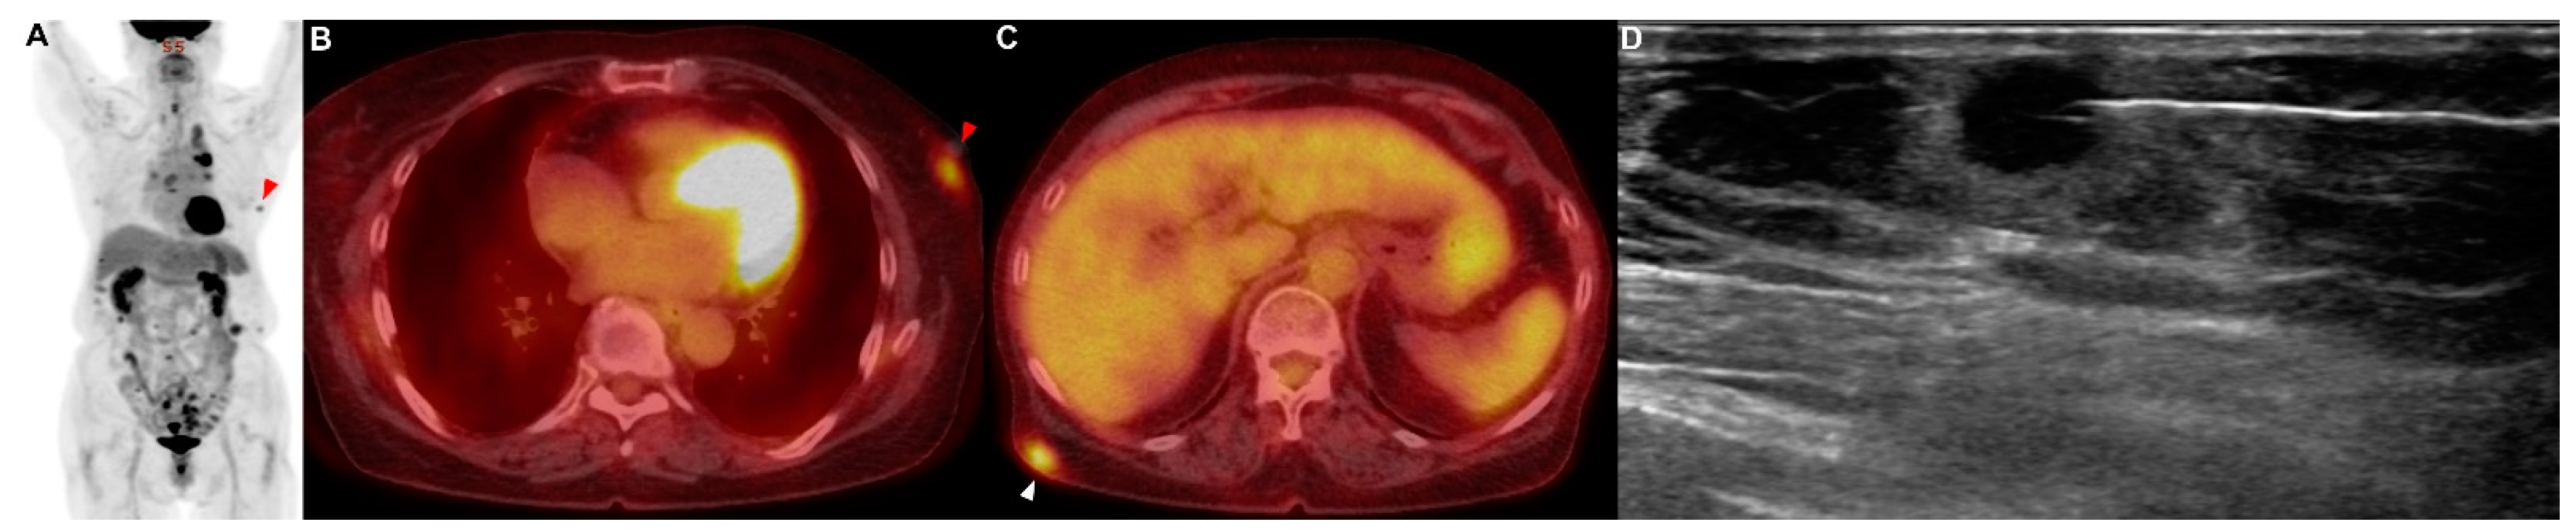

A 71-year-old man presented with a 2-week history of progressive dyspnea and chest discomfort. He had a history of 30 pack years of smoking and underwent surgery for cerebral hemorrhage 7 years ago. He stated that he did not take any medications or have other illnesses, including cardiovascular, allergic, rheumatic, or respiratory conditions. A contrast-enhanced computed tomography (CT) scan of his chest showed a lung mass invading the lobar bronchus of the right middle lobe. A bronchoscopic biopsy was performed, and poorly differentiated NSCLC was diagnosed. If there was no metastasis, the tumor was considered stage IIIB as T4N2. There was no suspicious finding of distant metastasis except for a hypermetabolic lesion (SUVmax = 4.76) of the pancreas tail, which was observed using positron emission tomography/computed tomography (PET/CT) (Figure 1A–C). Aspiration cytology was performed from the lesion of the pancreas tail through endoscopic ultrasound-fine needle aspiration (EUS-FNA) (Figure 1D). As a result of the cytological examination, a poorly differentiated non-small-cell carcinoma with the same morphology as the cancer cells in the lung cancer tissue was confirmed in the aspirated specimen (Figure A1A). This patient was treated with six courses of platinum-based chemotherapy (gemcitabine and cisplatin) for stage IV NSCLC.

Figure 1. Patient 1: a 71-year-old man diagnosed with non-small-cell lung cancer (NSCLC) with a solitary metastasis in the tail of the pancreas. (AC) Positron emission tomography/computed tomography (PET/CT) showed a solitary metastatic lesion (red arrowhead) in the tail of the pancreas. (D) EUS-FNA was performed at the metastatic lesion (red arrowhead) in the pancreas.